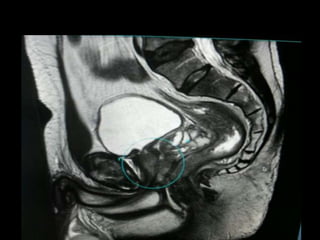

RM BACIAxPELVE

PROSTATA

CÂNCER DE PROSTATA

-Câncer mais comum

do homem.

-2ª causa de morte por

câncer do homem.

-Aumenta com a

idade.

-Metástases

METÁSTASE

CÂNCER DE COLO DO ÚTERO